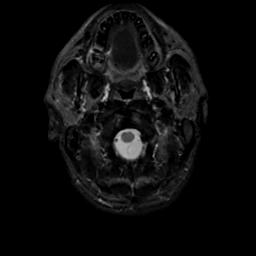

MR Study #8, March 31, 1991 -- Slice #1

[Home][Help][Clinical][Tour 1][Tour 2] Slice 1